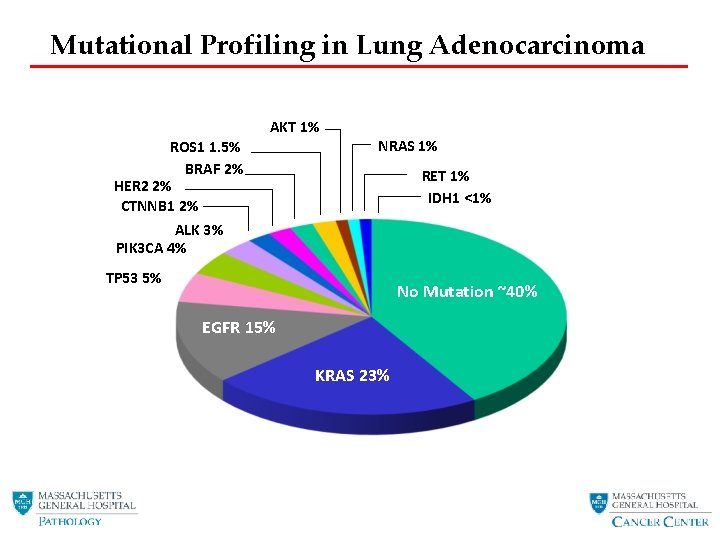

Mutational Profiling in Lung Adenocarcinoma AKT 1% ROS 1 1. 5% BRAF 2% HER 2 2% CTNNB 1 2% ALK 3% PIK 3 CA 4% NRAS 1% RET 1% IDH 1 <1% TP 53 5% No Mutation ~40% EGFR 15% KRAS 23%